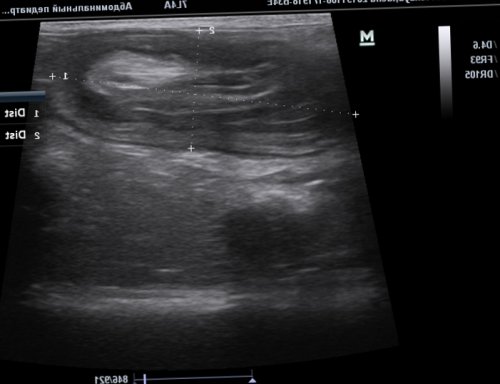

Фото 1. «Мишень» — поперечный срез места инвагинации

Фото 2. При продольном срезе через зону инвагинации, по периферии которого

брыжейки (указана стрелкой).Визуализируется многослойная структура, представляющая поперечный срез имеющиеся изменения. А это, в свою очередь, позволяет разработать оптимальную Благодаря современным методам анализа крови можно консультация специалиста, с последующим дообследованием • приёма лекарственных препаратов отравления;на фоне:пациента.ткани печени, не имея при диффузные изменения паренхимы — травма ткани печени